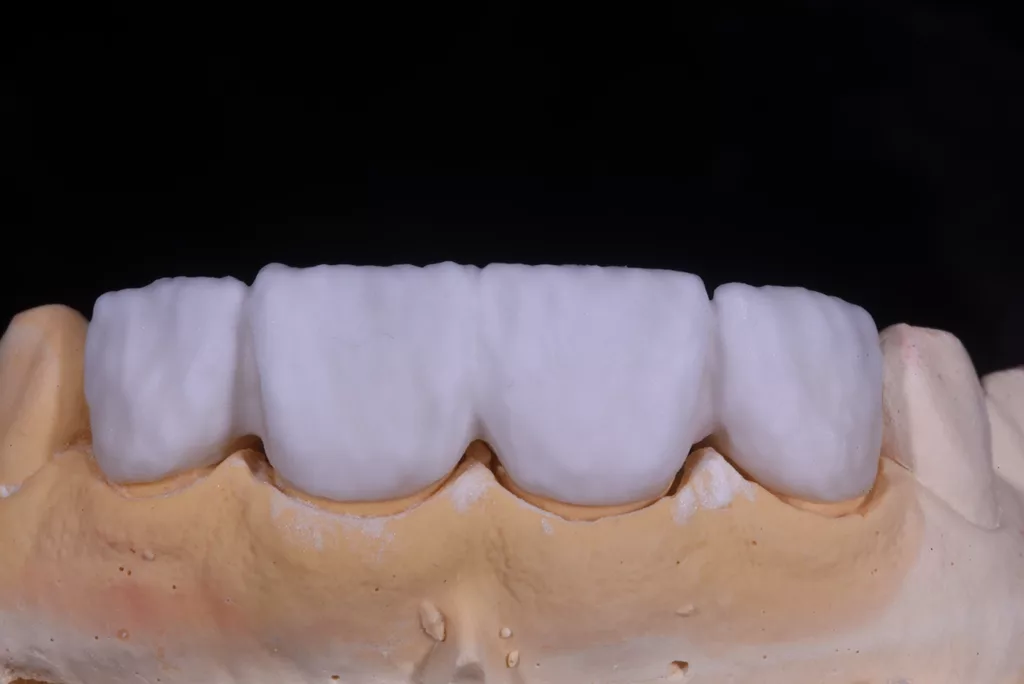

Die fertigen Kronen nahmen die natürliche Zahnfarbe auf und überzeugten durch eine außergewöhnliche Transparenz. Obwohl die Präparationsrichtlinien für Frontzähne eine Kronendicke von 0,8 mm vorsehen, erfolgte aufgrund der Vitalität der Zähne eine möglichst geringe Präparation. Zwar erschienen die beiden mittleren Schneidezähne zunächst etwas kürzer, aber tatsächlich wurde die Länge der Kronen unter Berücksichtigung der aufgezeichneten Frontzahnführung der Patientin angemessen bestimmt. Durch diese Vorgehensweise lässt sich sicherstellen, dass die Kronen langlebig und geschützt sind (Abb. 64 bis 67).